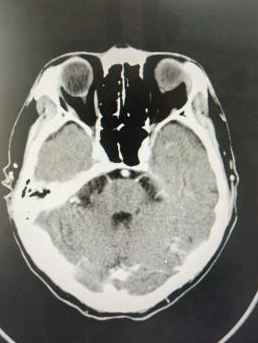

一位因反复头痛就诊的患者,经CT血管成像检查,确诊为颅内巨大动脉瘤,形态不规则,破裂风险极高。面对这一急危重症,孔令超与当地医生共同分析病情,制定诊疗方案。

通过对该病例影像特征的细致观察与风险分层评估,孔令超对巨大动脉瘤的形态学特点、破裂风险因素及介入治疗适应证有了更系统的认识。结合自身技术优势,完成全脑血管造影术,拓展了他在脑血管疾病领域的临床视野,也为科室今后开展动脉瘤介入治疗积累了宝贵经验。